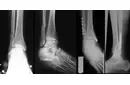

- Kırıklar: Osteoporoz gibi hastalıklar, kemiklerin kırılma riskini artırır. Özellikle yaşlı bireylerde bu durum sık görülmektedir.

- Görüntüleme yöntemleri: Röntgen, MRI (Manyetik Rezonans Görüntüleme) ve CT (Bilgisayarlı Tomografi) gibi yöntemler, kemik yapısını değerlendirmek için kullanılır.

- Cerrahi müdahale: Gerekli durumlarda, kemik onarımları veya eklem değişimi gibi cerrahi işlemler düşünülebilir.